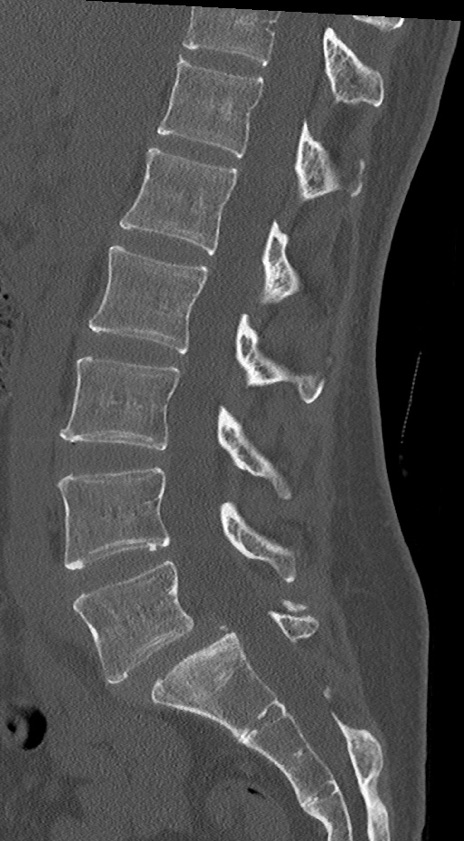

【整形】TIPS症例4 腰椎CT(矢状断像)

腰椎CT

横断像